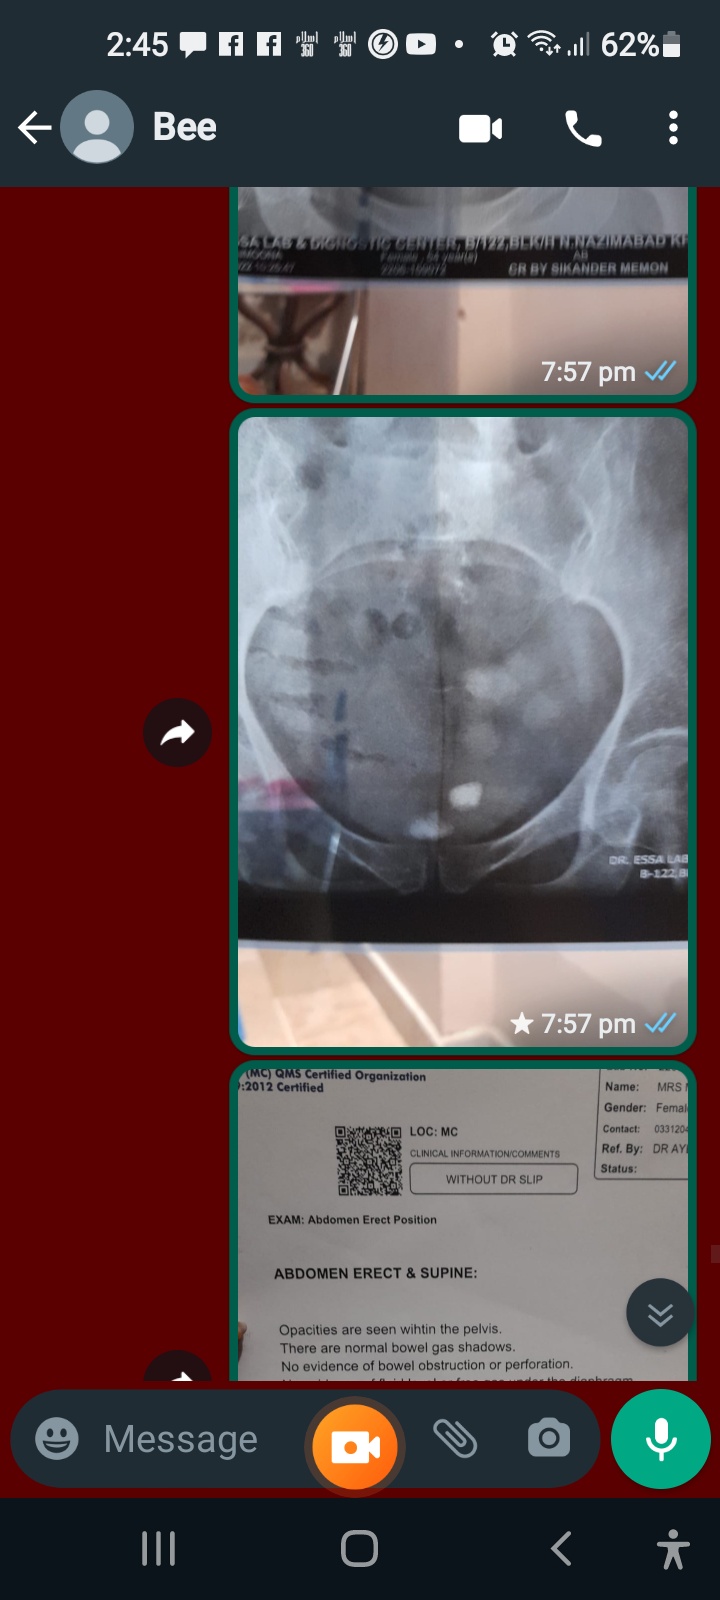

Attach Photo here: